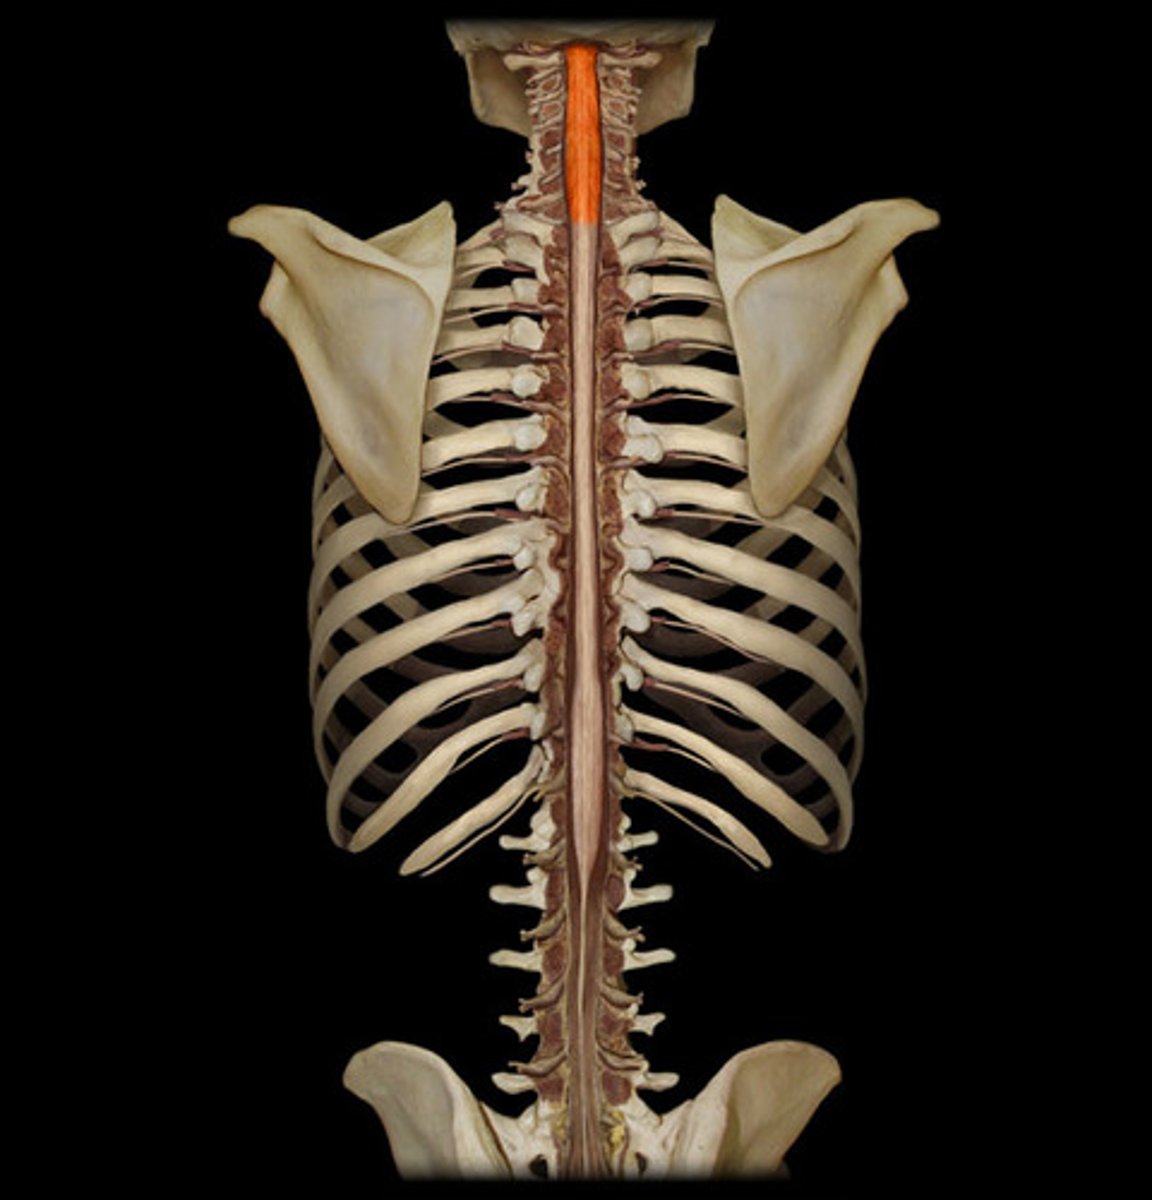

spinal cord

a major part of the central nervous system which conducts sensory and motor nerve impulses to and from the brain; housed within the vertebral canal

cervical region of spinal cord

supplies neck, shoulders, and upper limbs, C1-8

thoracic region of spinal cord

supplies thoracic cage, T1-12

lumbar region of spinal cord

supplies hips & front of lower limbs, L1-5

sacral region of spinal cord

supplies buttock, genitalia, and backs of lower limbs, S1-5

conus medullaris

inferior tapered end of spinal cord

cauda equina

collection of spinal nerves below the end of the spinal cord; below L1 vertebrae

filum terminale